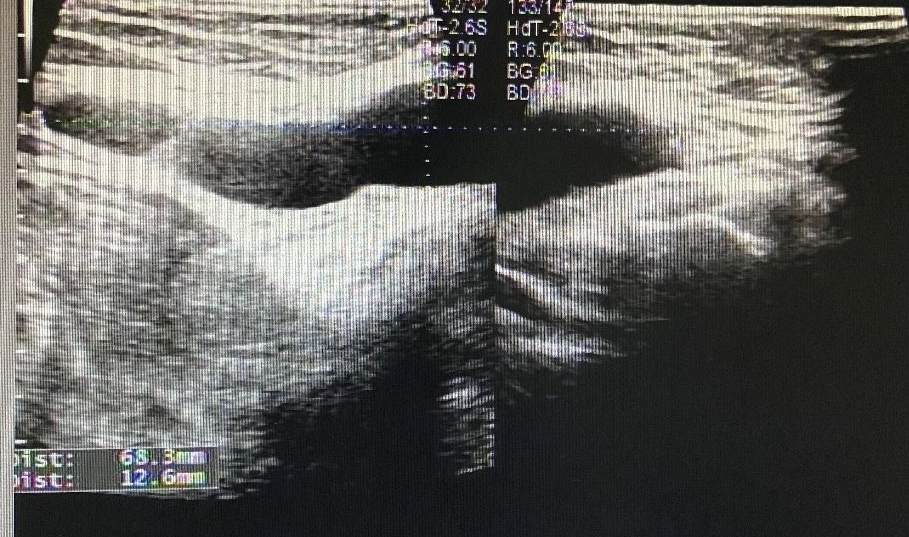

Case 3

图 6 左侧腹股沟区包块

图 7 左侧腹股沟区包块

超声所见

左侧腹股沟区见范围约 7.5cm×4.7cm×4.2cm 无回声区,透声尚可,平卧位变化不明显。右侧腹股沟区未见明显异常回声。

超声提示

左侧腹股沟无回声区,子宫圆韧带囊肿?

术后证实为左侧子宫圆韧带囊肿。